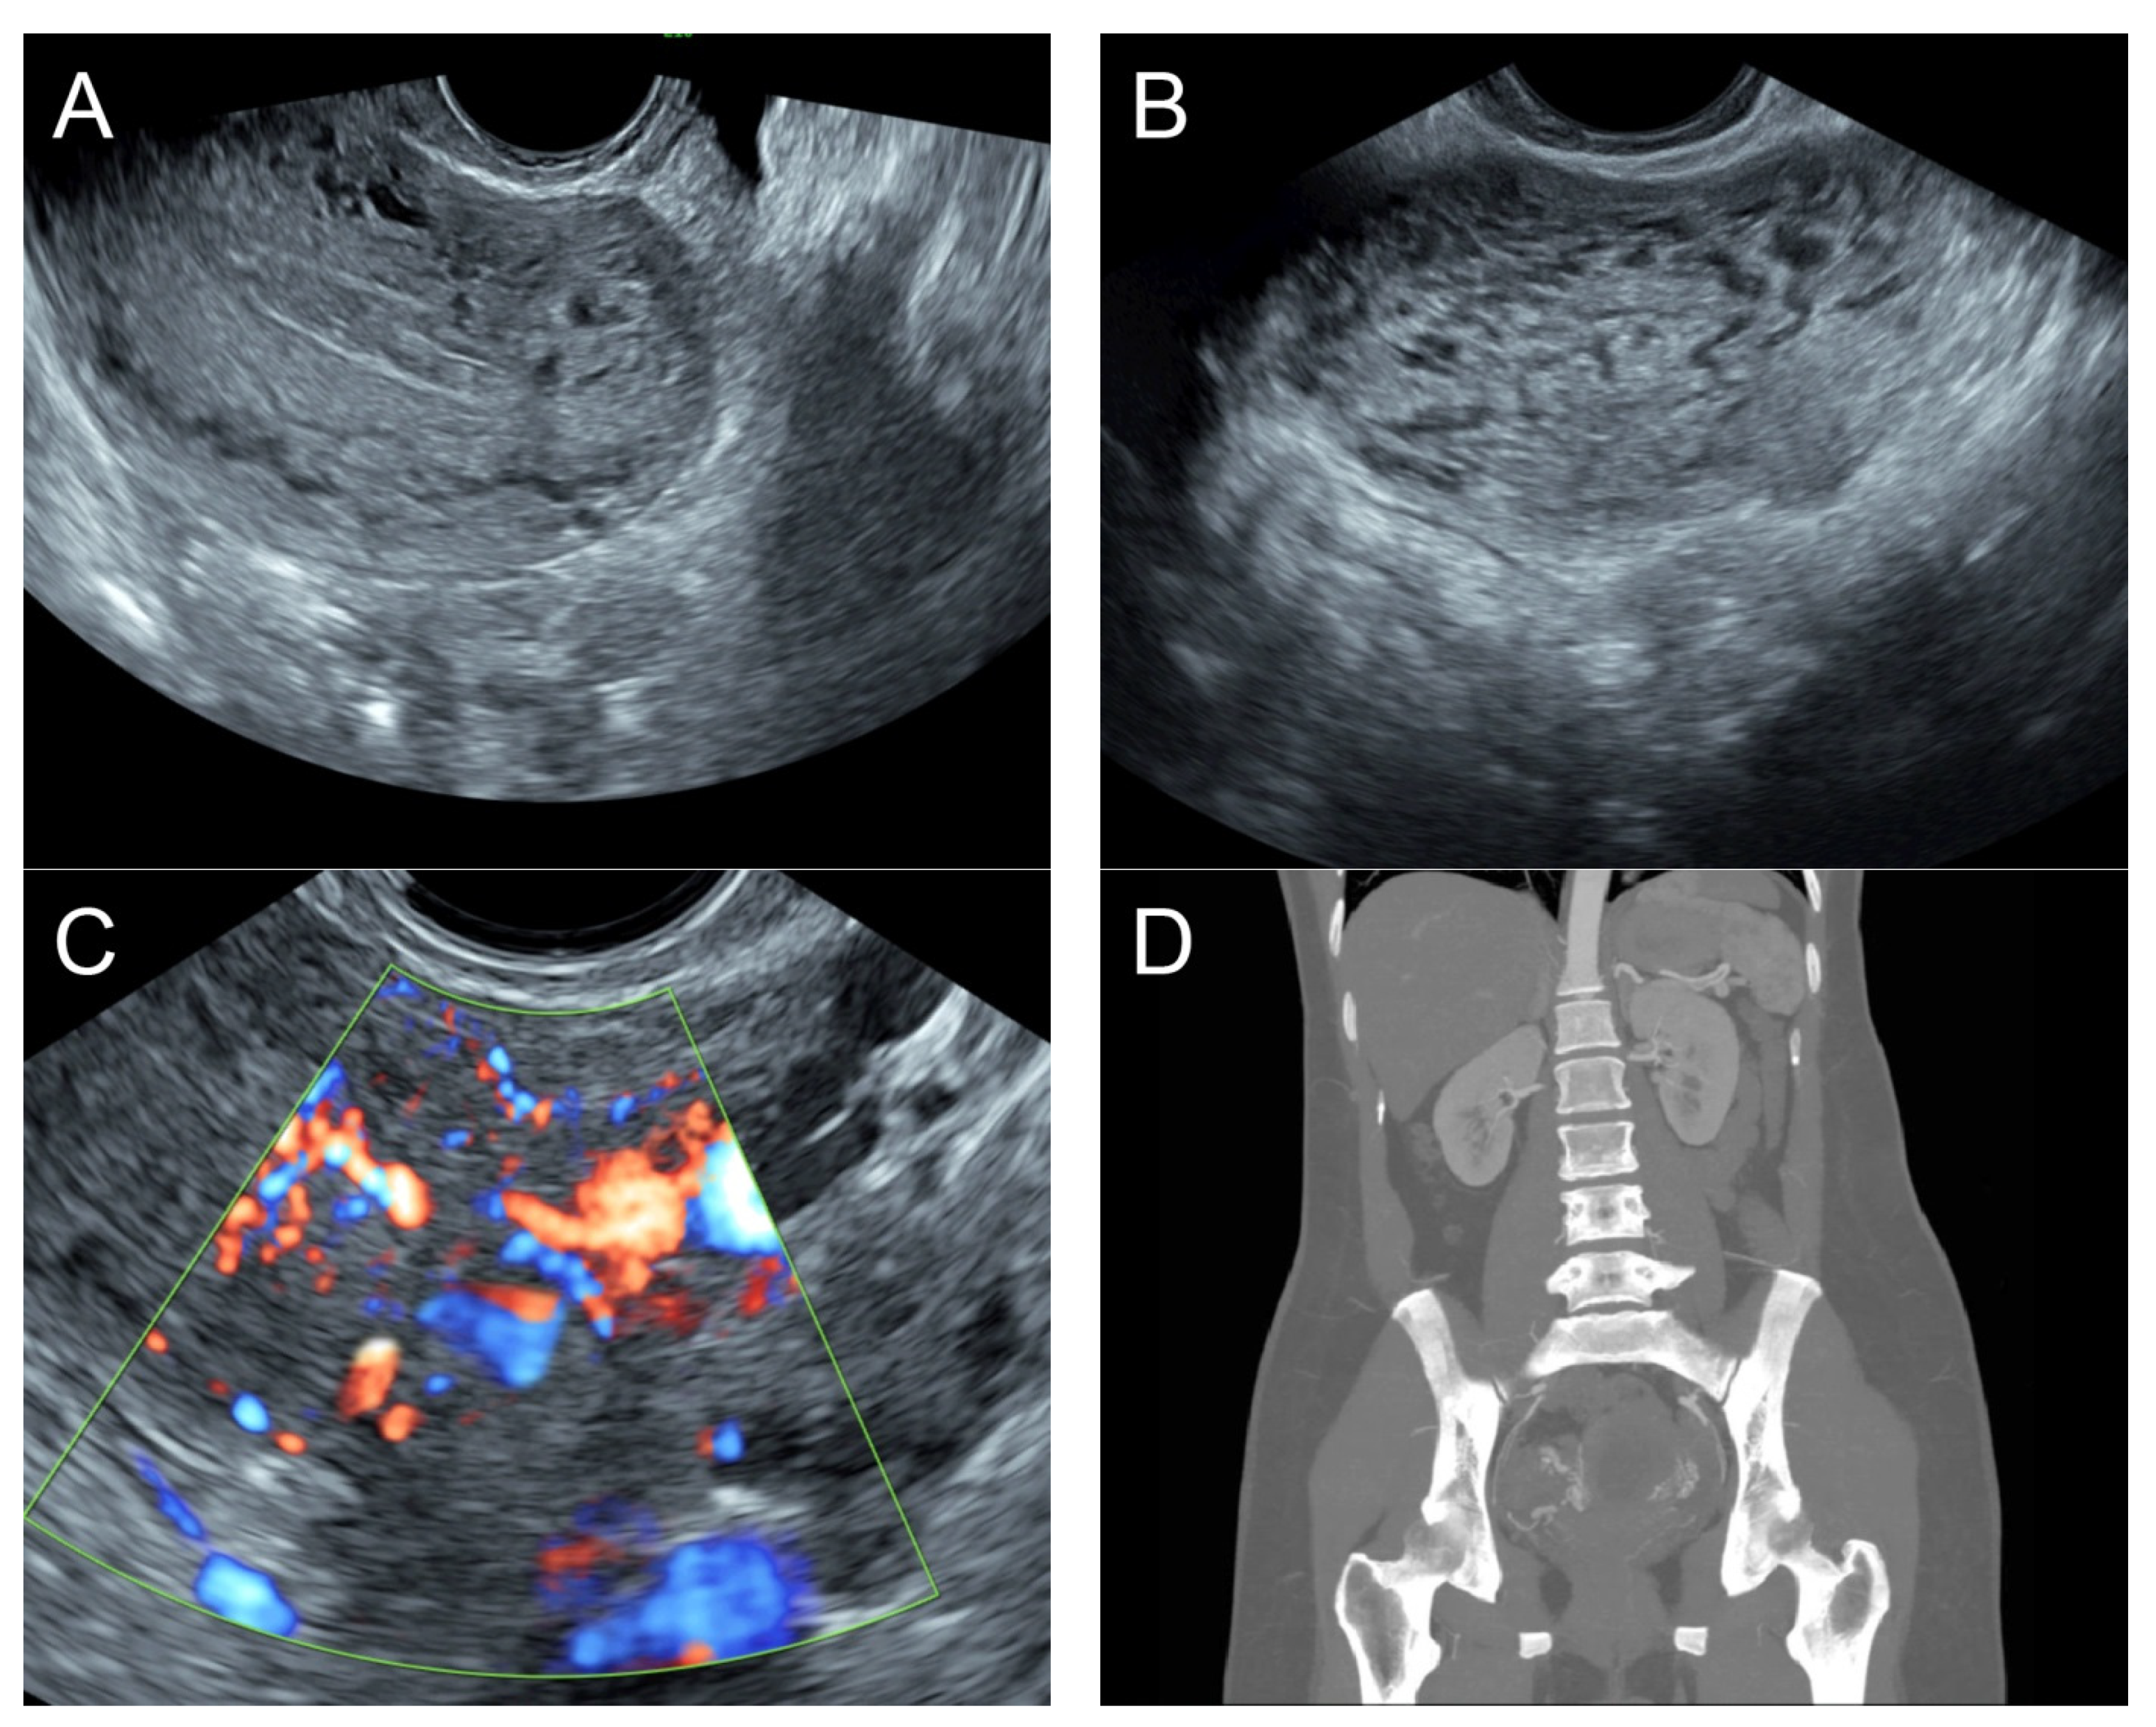

(A) Transabdominal grayscale ultrasound: transverse scans of suprapubic area showed suboptimal-quality image of the uterus, which displayed ill-defined soft tissue mass, non-visualized endometrial lining, hypoechoic areas of the uterus. No normal architecture of the uterus could be demonstrated. (B) Color flow mapping (the same area of figure (A)) showed markedly vascularized uterus, involving throughout the uterus intense vascularity with a chaotic, multidirectional flow. (C) Transvaginal color Doppler ultrasound showed markedly vascularized uterus, involving throughout the uterus intense vascularity with a chaotic, multidirectional flow. (D) Abdominal CTA revealed innumerable tortuous dilated vessels in the pelvic cavity, along the entire uterine wall. The lesions were fed by multiple arterial feeders, which were displayed as tortuous dilated arteries of the bilateral uterine arteries, right ovarian artery, and right inferior epigastric artery. Multiple draining veins demonstrated early venous opacification, namely the bilateral internal iliac veins and right ovarian vein. The CTA findings confirmed uterine AVM.